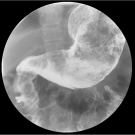

An 11-year-old girl presented to the emergency department with a 2-week history of nausea and vomiting in the context of chronic abdominal pain, diarrhea, and unintentional weight loss.

07/11/2019